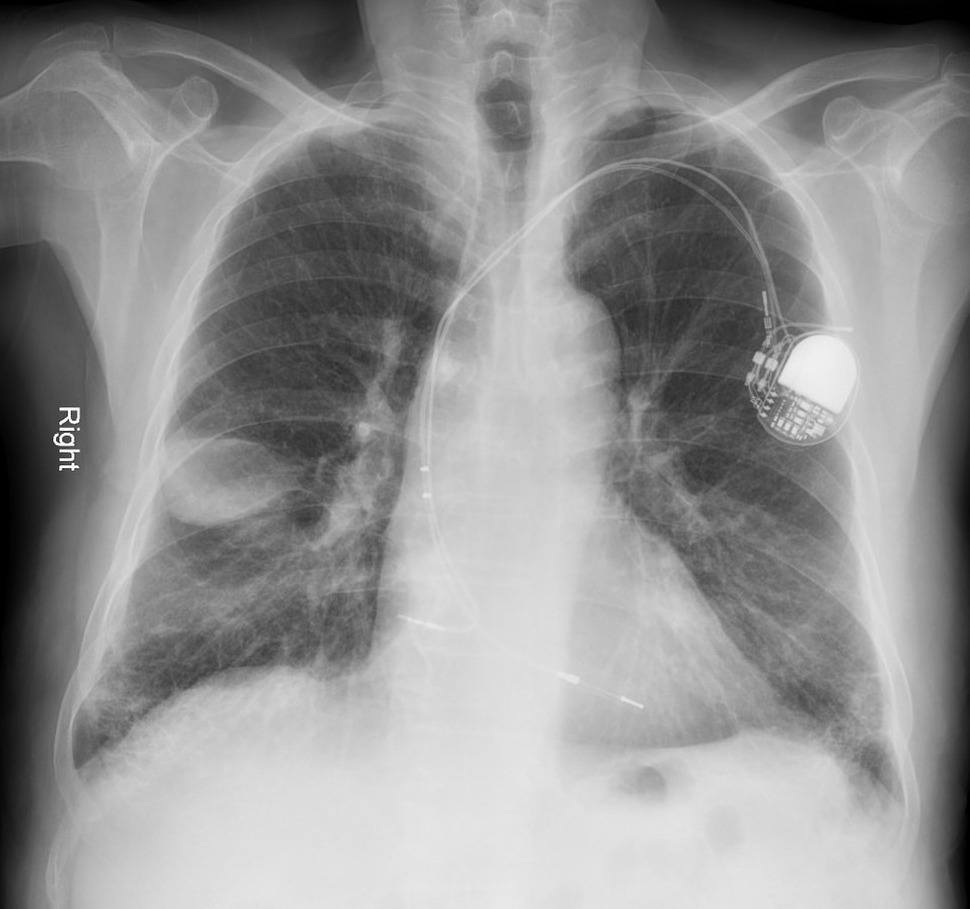

Tràn dịch màng phổi

Tràn dịch màng phổi - Ảnh 2

Tràn dịch màng phổi - Ảnh 3

» Thông tin: Nam giới – 46 tuổi.

» Lâm sàng: Ho + tức ngực.

# Tràn dịch rãnh liên thùy phụ phổi phải.